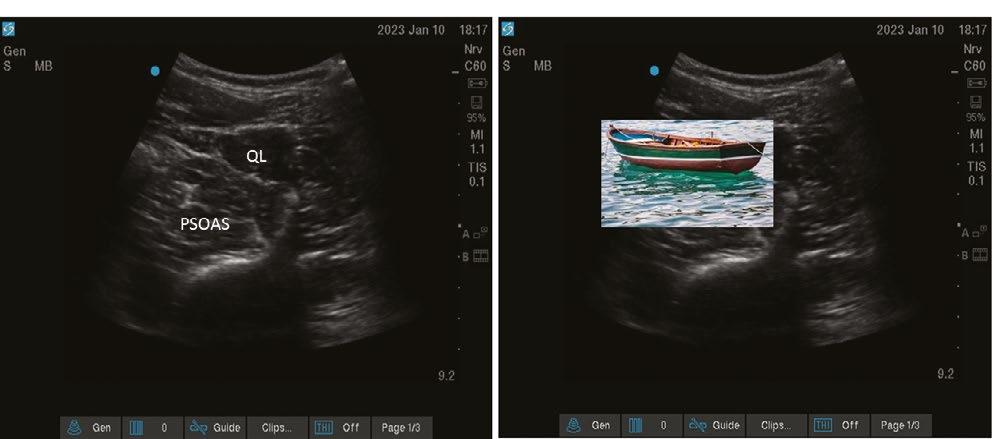

Another focus for AI in anaesthesia lies in real-time analysis of ultrasound scanning.[8] Multiple algorithms have been developed to segment and apply colour to greyscale ultrasound live images. Despite promising progress, the evidence base gathered to assess and appraise the utility of these various tools remains insufficient. Studies are too heterogenous, use differing performance metrics and ground truth definitions, or are simply not made public due to commercial sensitivity.[9]